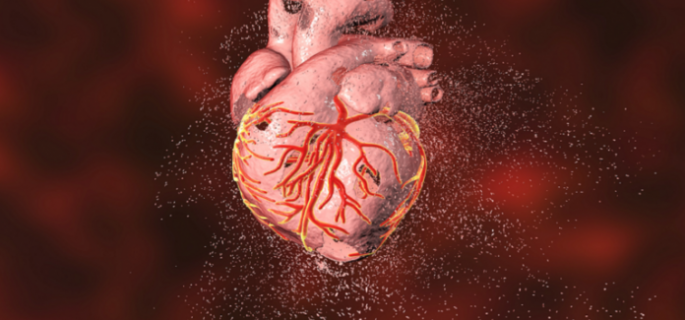

وتؤثر أمراض القلب على كل وظائف القلب وأجزائه، وتشمل هذه الحالة مجموعة من الأمراض، بما في ذلك، أمراض الأوعية الدموية مثل مرض الشريان التاجي، ومشكلات نظم القلب (عدم انتظام القلب)، وبعض عيوب القلب التي يولد بها الشخص (عيوب خِلقية في القلب)، ومرض صمام القلب، واعتلال عضلة القلب.